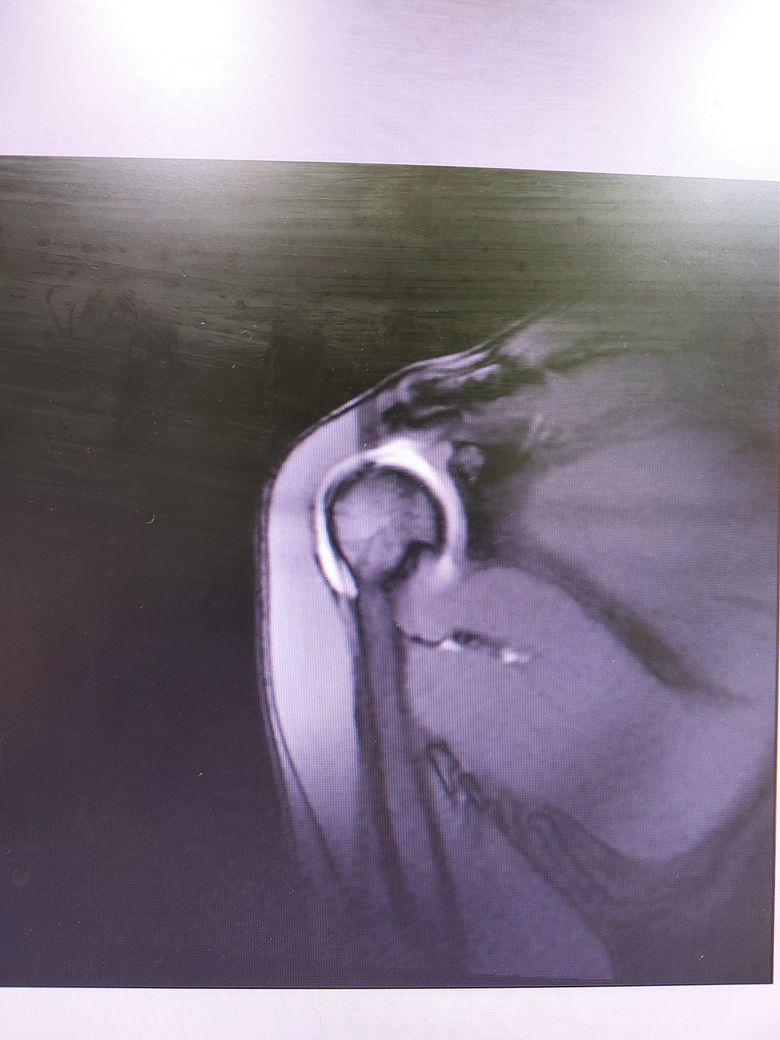

팔이 잡아당겨지는 사고 이후 통증이 지속되어

조영제 투입 후 mri 촬영을 하였습니다.

진단명은 상부관절와순파열(슬랩)이며

슬랩이 맞나요? 맞다면 파열 진행 정도는 어느정도인지..